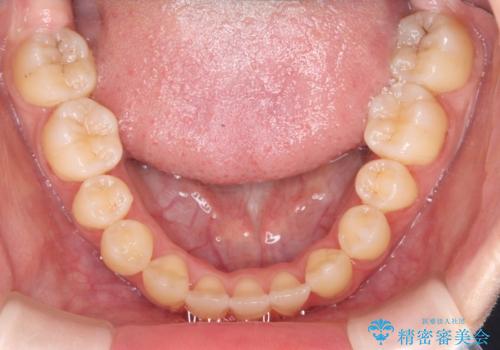

転院という不安な状況にある患者様のストレスを最小限に抑えつつ、歯の健康を最優先にした処置を行いました。

装置の変更と歯肉への配慮: ワイヤー矯正は歯の根(歯根)を平行に移動させる「歯体移動」を得意としています。本症例では、歯肉退縮を防ぐために、歯の傾きを精密にコントロールしながら抜歯スペースを閉じる必要がありました。ワイヤー装置を用いることで、インビザラインでは難しくなっていた三次元的な細かい調整を可能にしました。

リカバリーのプロセス: 適合が悪くなったインビザラインを一旦中止し、ブラケットを装着。停滞していた歯の移動を再開させ、上下の正中(中心)や奥歯の咬み合わせを一つひとつ整えていきました。